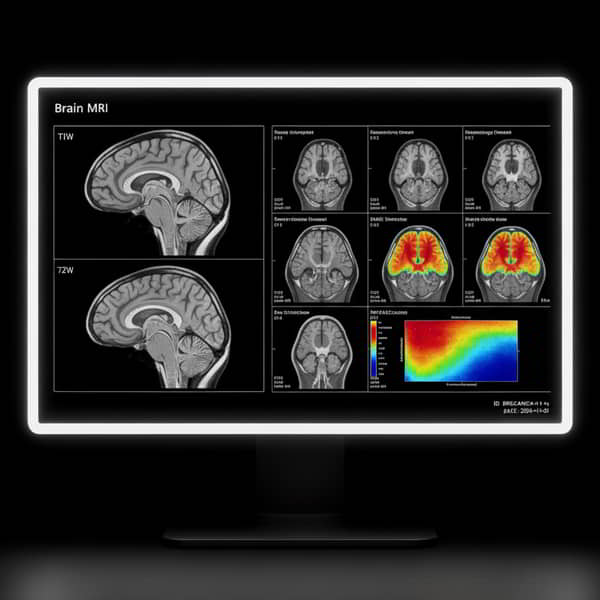

Evaluamos el encéfalo/cráneo con imágenes de alta resolución y sin radiación ionizante. Operamos en Lince, Lima (Perú) con Signa™ Prime 1.5 Tesla + AIR™ Recon DL (IA) para reducir ruido, acortar tiempos y mejorar el confort. Informamos con enfoque neurorradiológico y entrega digital/impresa.

En PREVEN realizamos resonancia magnética de cerebro/encéfalo (RMN de cráneo) para ACV, tumores, aneurismas/malformaciones, infecciones, epilepsia, cefalea, trauma y deterioro cognitivo. Trabajamos con Signa™ Prime 1.5T + AIR™ Recon DL (IA), Silent Scan para menor ruido y protocolos adaptados a tu indicación clínica.

La RMN de encéfalo/cráneo es un examen no invasivo que usa campos magnéticos y radiofrecuencia para generar imágenes del parénquima cerebral, sustancia blanca, vasos y cisternas. Integra T1/T2, FLAIR, DWI/ADC y, cuando cambia la conducta, contraste con gadolinio.

Según el motivo clínico, añadimos SWI, T1 3D isotrópico, MRA/MRV y otras herramientas avanzadas. La información guía diagnóstico, estadios y seguimiento, y ayuda a decidir si se requieren biomarcadores o estudios complementarios.

EQUIPO DE 1.5T CON INTELIGENCIA ARTIFICIAL (IA) EN 3D

En Prevén, trabajamos con un Resonador Magnético con software AIR™ Recon DL; un algoritmo de reconstrucción en equipos General Electric.

Equipos de RM con IA permiten reducir tiempos de estudios hasta un 64% manteniendo la calidad de imagen.